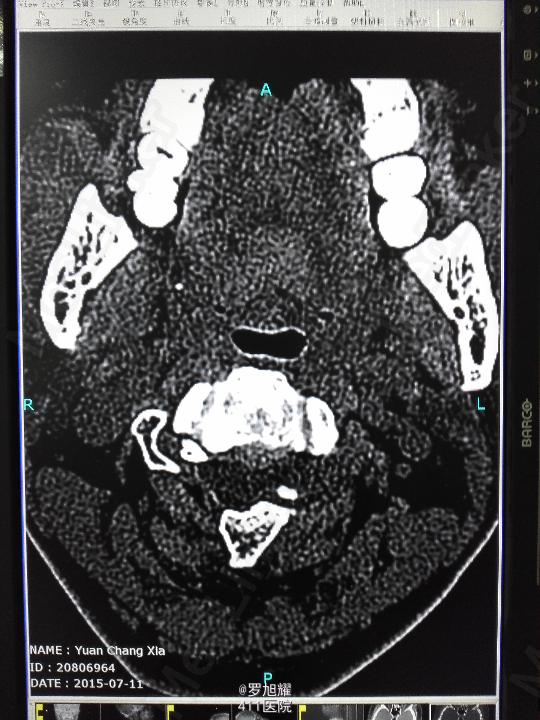

右侧躯体麻木1年,右上肢及下肢麻木2月余。 查体:颈椎活动受限,右上肢肘关节以远痛温觉减退,右侧胸4平面以下痛温觉及触觉减退,四肢肌力尚可,右侧霍夫曼征阳性,右侧上下肢所有腱反射亢进。 颈椎X线示:颈2椎板棘突缺如,颈3棘突肥大增高。 颈椎CT示:颈2椎板棘突缺如,颈3棘突肥大增高,颈2/3椎间盘突出,左侧颈2残留部分椎板进入椎管。枢椎齿突增生,寰枢关节退变。 颈椎MRI示:颈2/3椎间盘突出,左侧颈2椎板进入椎管,颈髓受压变性。

查体:颈椎活动受限,右上肢肘关节以远痛温觉减退,右侧胸4平面以下痛温觉及触觉减退,四肢肌力尚可,右侧霍夫曼征阳性,右侧上下肢所有腱反射亢进。 颈椎X线示:颈2椎板棘突缺如,颈3棘突肥大增高。 颈椎CT示:颈2椎板棘突缺如,颈3棘突肥大增高,颈2/3椎间盘突出,左侧颈2残留部分椎板进入椎管。枢椎齿突增生,寰枢关节退变。 颈椎MRI示:颈2/3椎间盘突出,左侧颈2椎板进入椎管,颈髓受压变性。